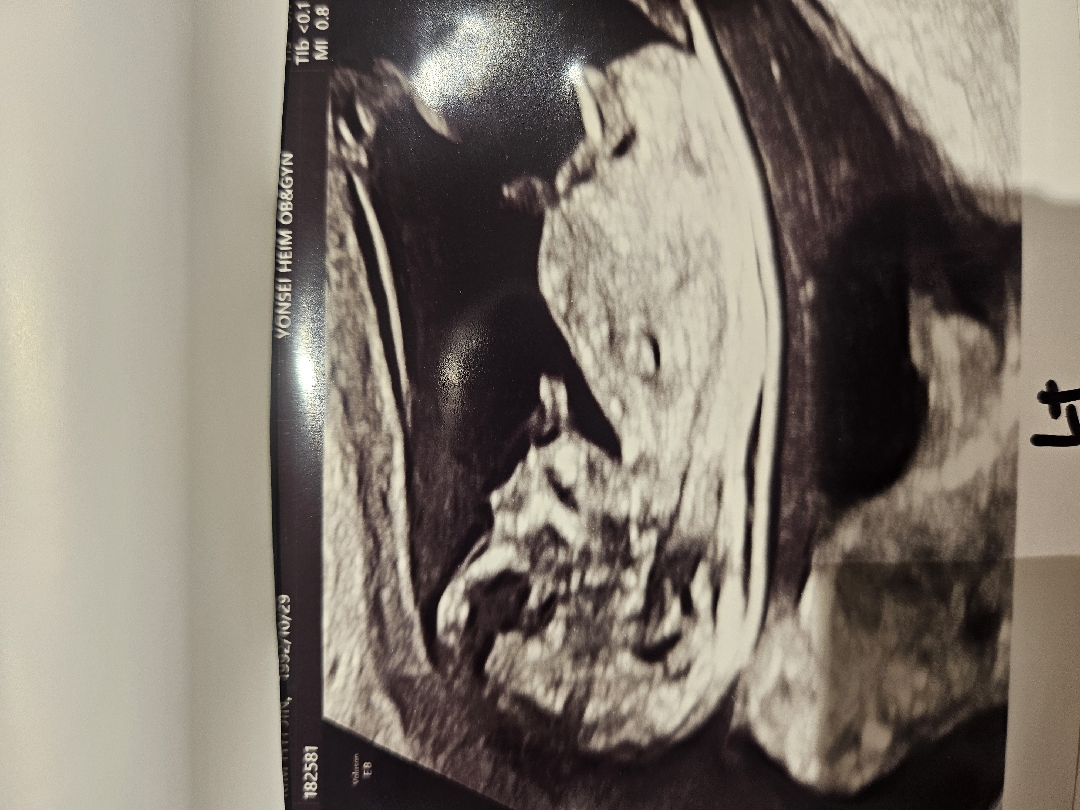

12주차 각도법 궁금합니다 일란성쌍둥이입니다